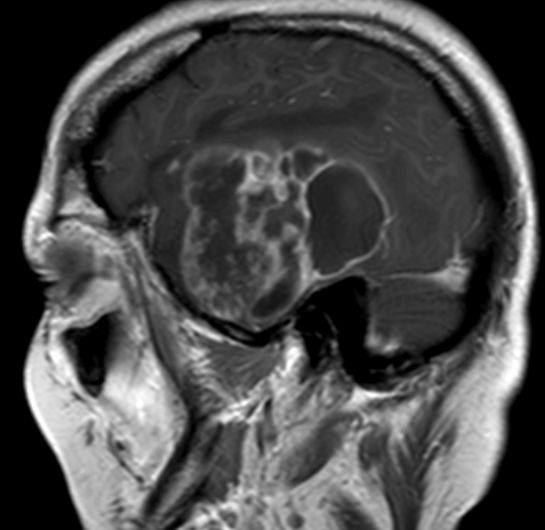

Schmetterlingsgliom des hinteren Balkens |

62-jähriger Mann mit torkeligem Gang, Amnesie und Verwirrtheit. Schmetterlingsgliom des hinteren Balkens.![]() |

![]() |

![]() | |